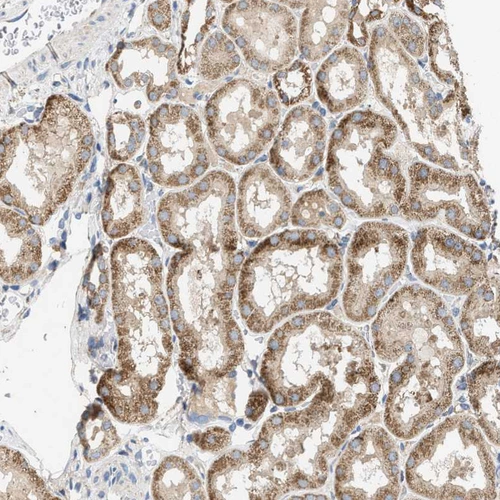

Immunohistochemical staining of human heart muscle, kidney, liver and testis using Anti-OXSM antibody HPA021300 (A) shows similar protein distribution across tissues to independent antibody HPA021293 (B).